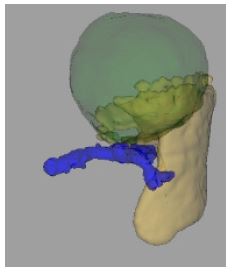

We scheduled a multidisciplinary discussion with surgeons, radiologists and paediatricians and decided to manage the cystic lesion by laparoscopic partial splenectomy with ultrasound guidance. The patient had been previously vaccinated for encapsulated bacteria and was prescribed perioperative antibiotic prophylaxis with cefazoline and anti-thromboembolic prophylaxis with enoxaparin. The operation was performed under general anaesthesia. The patient was placed in a supine position on the operative table and we placed four trocars (three 5 mm trocar and one 15 mm trocar) as described in previous works [6]. The exploration of the abdomen showed a cystic lesion of the upper pole of the spleen (Figure 3). IOUS was performed, marking the margins of the lesion and confirming the absence of further cysts. After division of the gastrosplenic ligament and mobilization of the posterior spleen’s attachments, we emptied the cystic lesion with a needle and collected about 50 ml of clear fluid. We coagulated the feeding vessels with a radiofrequency device (LigaSure™ Medtronic) keeping a 1 cm distance from the margin of the lesion as identified with IOUS until we obtained an ischemic demarcation of the splenic parenchyma. The transection of the parenchyma was then performed, under IOUS guidance, using the radiofrequency device. A bipolar coagulation device (Aquamantys™ bipolar sealers Medtronic) was used for haemostasis (Figure 4). The residual spleen was estimated to be about a third of the entire initial splenic volume (Figure 5). A laparoscopic stitch was placed in order to fix the remaining spleen to the omentum and avoid a possible torsion of the pedicle’s vessels and subsequent ischaemia of the residual organ.

Figure 5: CT-based calculation of the volume of splenic parenchyma (yellow colour) and cyst (green colour) using Philips HealthCare® Program. The splenic vein is indicated with the blue colour.